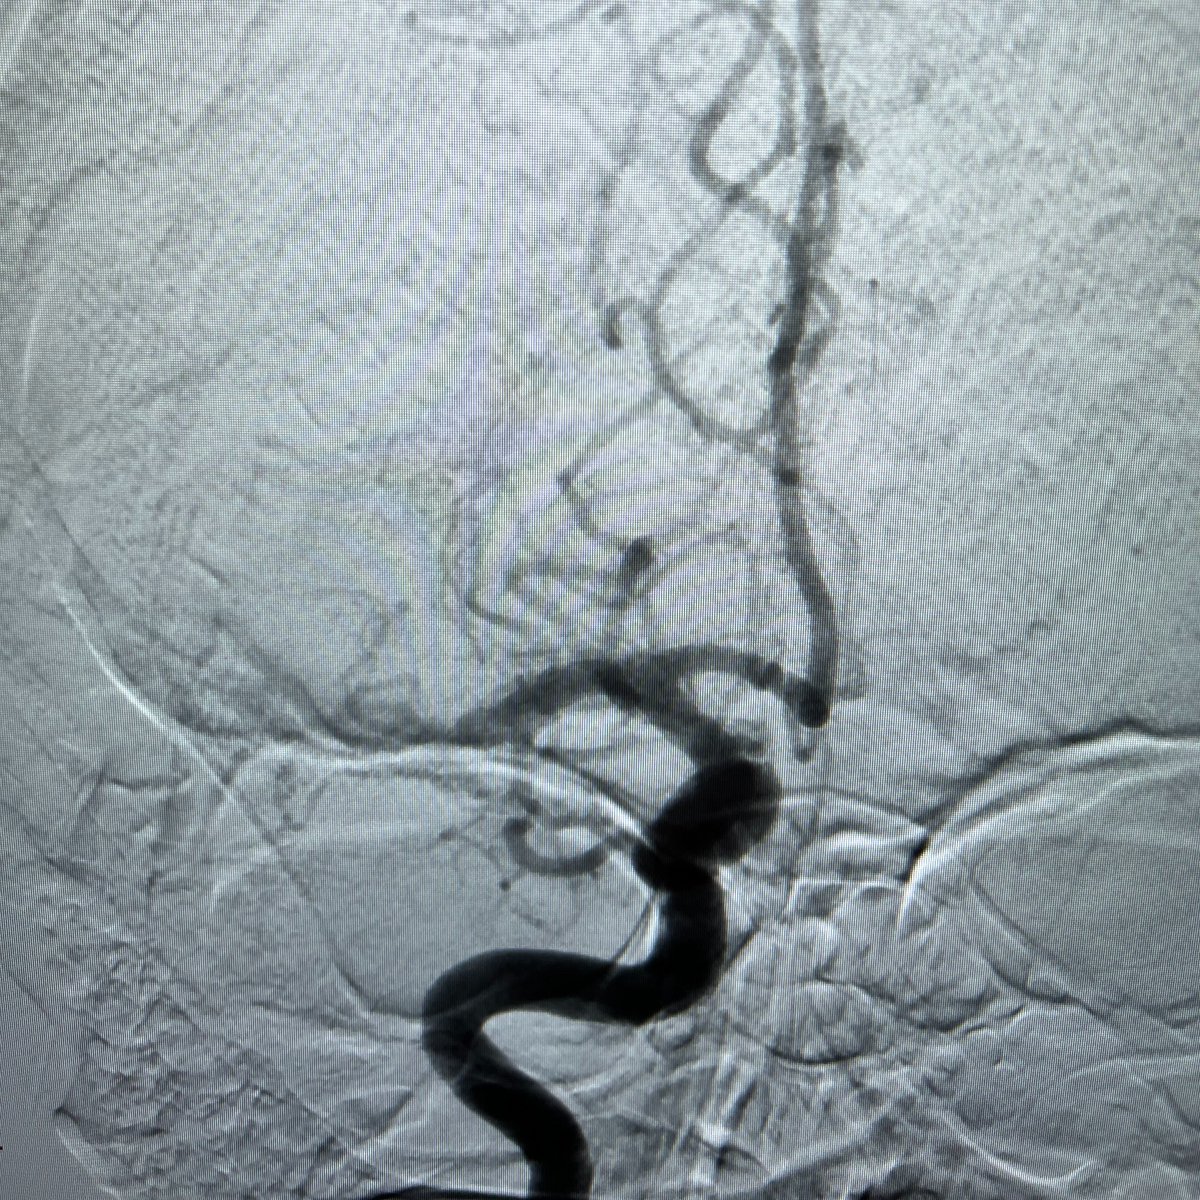

ICYMI, here’s a snapshot from the #Comaneci Acomm embolization broadcast, saving the patient from long-term DAPT. "This was a really good result for a really difficult case. We could not have done this any other way without Comaneci." - Dr. Phil Taussky, University of Utah Neurosurgery.